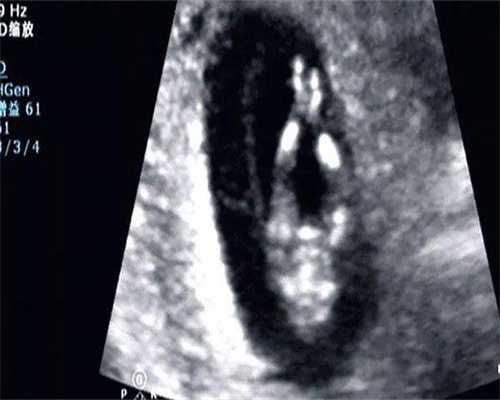

4、女方试管、男方取精;

5、胚胎培养至囊胚期进行PGD筛查;

6、胚胎移植,等待验孕。